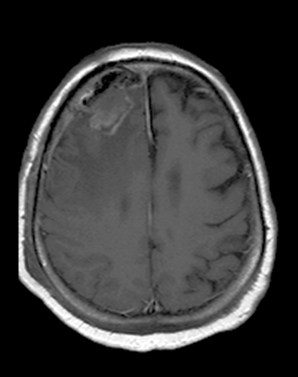

MRI: Meningiomas show a good Gadolinium enhancement with a characteristic “dural tail” sign (a thickening in the neighboring dura).

MRI has the greatest sensitivity in the detection of neoplastic brain lesions. The relaxation time of tumor is usually longer than that of the surrounding normal tissues. Therefore on T1W images neoplasms have slightly weaker signal intensity, while on T2W images they are more hyperintense than normal parenchyma. This signal pattern can be very characteristic and has great diagnostic value. However, secondary neoplastic signs, such as mass-effect of the tumor cannot be neglect either. A space occupying lesion can cause:

Besides the morphological signs, contrast enhancing properties are also characteristic.